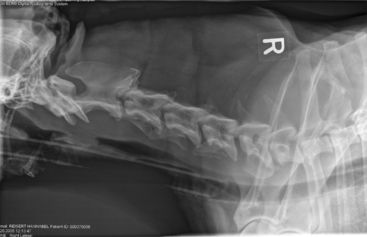

Figure 22-8 The effects of matrix and pixel size on image resolution are illustrated in this series of otherwise identical lateral cat abdominal radiographic images. A, A high-quality digital image with a high matrix size (e.g., 2048 pixels on the vertical axis × 2048 pixels across the horizontal axis). B, The matrix size is reduced to 64 × 64 pixels. Note that individual pixels can be seen as small squares, and the image has a pixilated appearance. C, The pixilation becomes noticeably worse when the matrix size is reduced to 32 × 32. D, The matrix size is only 16 × 16 pixels, and the image of the cat abdomen is no longer recognizable. Note that each pixel only represents a single shade of gray, dependent on bit number.